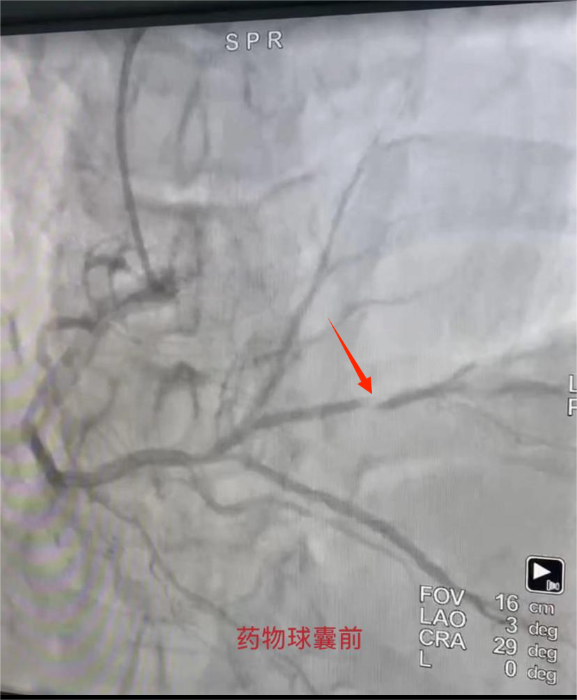

爲進一步明确病因,心血管病院二病區副主任張偉傑及醫生(shēng)馬玉娥行冠脈造影(yǐng)檢查,術(shù)中造影(yǐng)提示:右冠遠(yuǎn)端90%狹窄。張偉傑考慮狹窄部位屬于遠(yuǎn)端小血管病變,無相(xiàng)應支架可(kě)選,遂決定在病變部位給予藥物球囊治療。手術(shù)成功結束,張某再無心絞痛發作(zuò)。